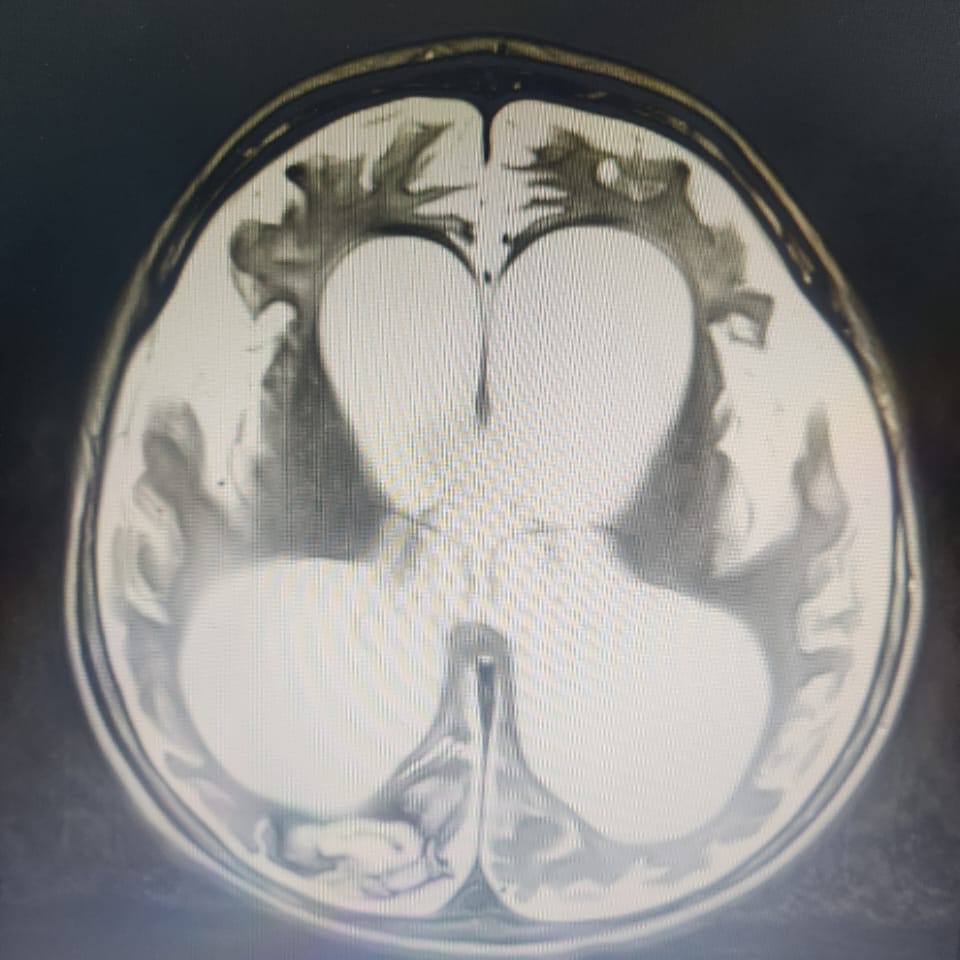

Saat usianya 8 bulan, Ryuga sudah didiagnosa kerusakan otak yang membuatnya tidak bisa mengontrol gerakan tubuh dan ototnya (Cerebral Palsy), serta didiagnosa infeksi pada bagian belakang tenggorokannya (Faringo).

Saat usianya 8 bulan, Ryuga sudah didiagnosa kerusakan otak yang membuatnya tidak bisa mengontrol gerakan tubuh dan ototnya (Cerebral Palsy), serta didiagnosa infeksi pada bagian belakang tenggorokannya (Faringo).